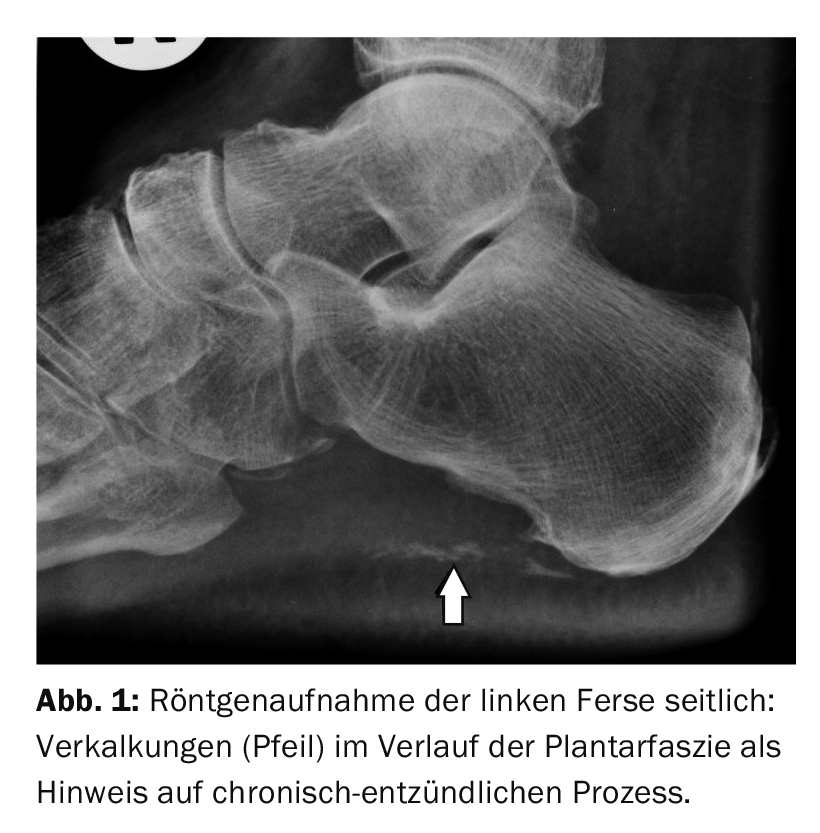

Os raios X em projecção lateral não podem captar a reacção inflamatória da fáscia plantar. Se um esporão de calcanhar plantar for visível, as pessoas tendem a pensar que é a causa dos sintomas. No entanto, é importante lembrar que a fascite e as esporas podem ocorrer simultaneamente. Se nenhum esporão de calcanhar for reconhecível, pode suspeitar-se de fascite plantaris como o gatilho das queixas dependentes da carga, muitas vezes também em combinação com fibroostites calcanei rarefactoras. As calcificações na área da fáscia plantar indicam um curso inflamatório crónico (Fig. 1).

No estudo de caso 1, a radiografia lateral do calcanhar direito mostra uma fasciopatia complexa num paciente de 70 anos com dores dependentes da carga na zona plantar e do calcanhar dorsal, bem como na zona do tarso com artrose. Os esporões do calcanhar plantar e dorsal, bem como as calcificações da fáscia plantar e na base do tendão de Aquiles são indicações de alterações inflamatórias degenerativas crónicas.